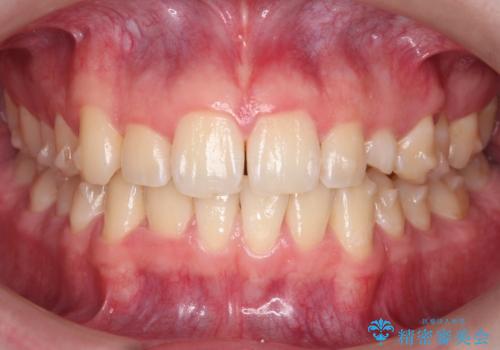

前歯のすき間、犬歯の異所萌出 乳歯を抜かずに矯正

- 前歯のすきまと八重歯を主訴に来院。

左上の乳犬歯が残っており、その下から生えてくるはずの犬歯(永久歯)が左上小臼歯部に萌出していました。

乳歯をそのまま並べたため、上顎の左右の犬歯の幅は非対称になっています。